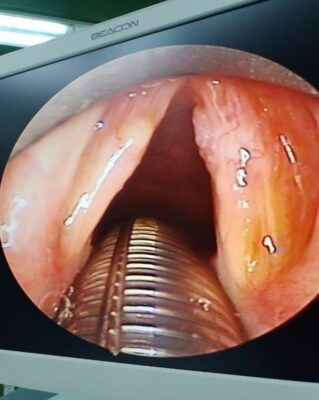

Hình ảnh :U nhú dây thanh (P)

U nhú dây thanh trái trước và sau phẫu thuật của bênh nhân Lê Thị Mỹ T